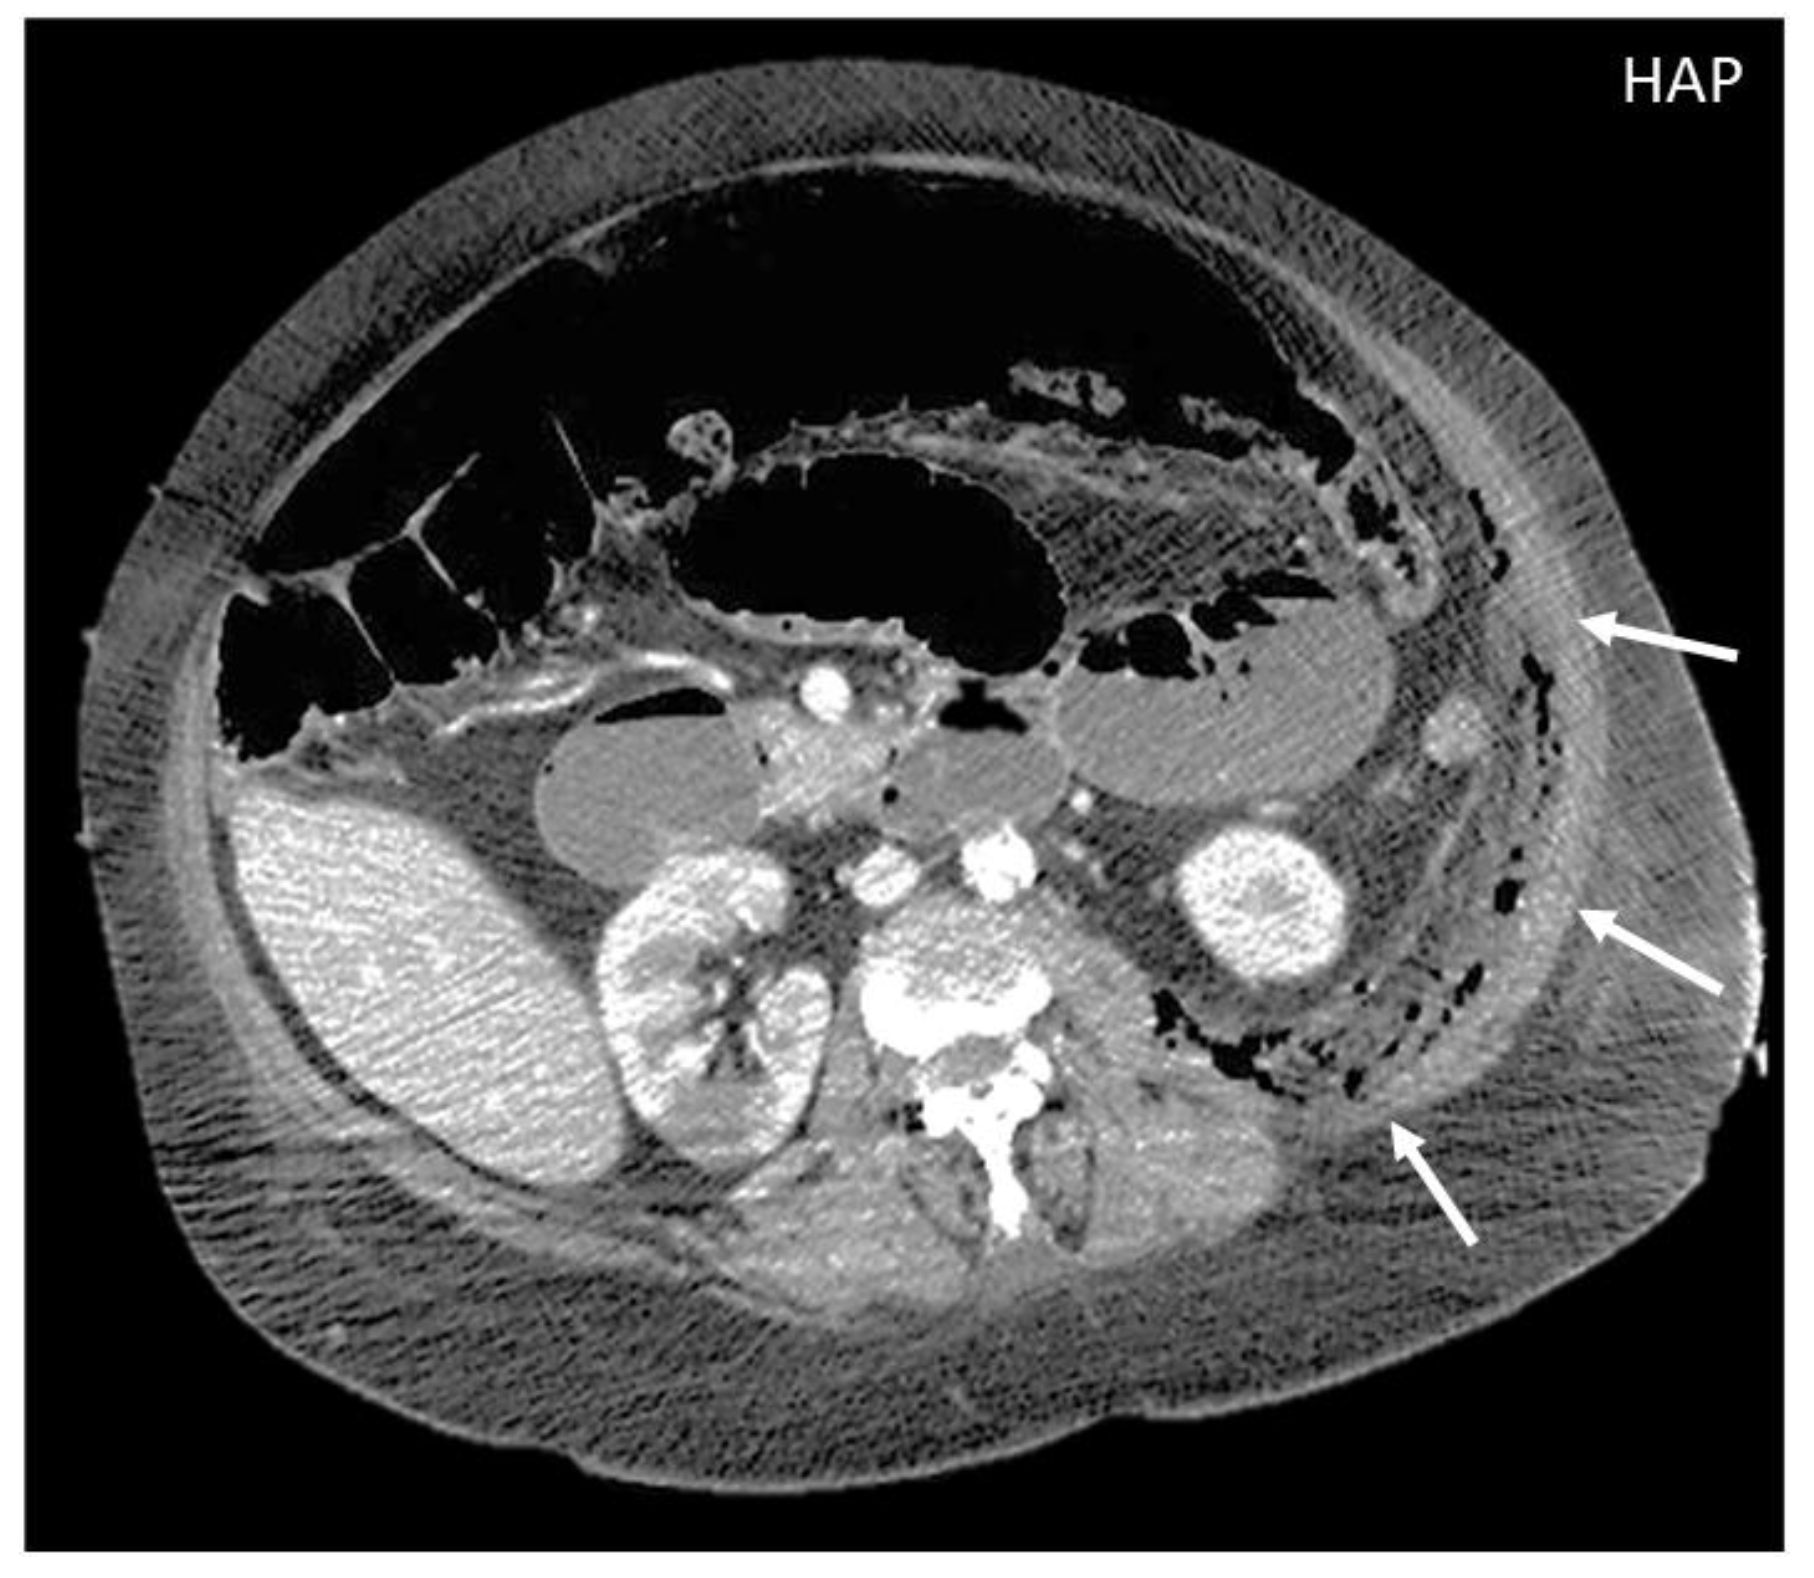

On CT, the most suggestive findings of NF are the thickening of the fascia and a large amount of subcutaneous gas, although the latter is not specific [10,11,12] (Figure 2).

Focal or diffuse non-enhancing areas [10,11] with extensive multi-compartmental involvement (meaning that at least three muscle compartments are involved in this change) are another typical finding.

Figure 2. CT appearance of necrotizing fasciitis in a 58-year-old woman with a recent left lower limb open wound who arrived at the ER in septic shock. Arterial phase axial CT scan reveals the presence of free air in the fascial planes of the left lateral and posterior abdominal wall, with fascial thickening and lack of muscular enhancement, as compared to its counterpart (arrows). These elements are suggestive of necrotizing fasciitis. The patient was promptly referred to surgery, but she died on the operatory table.